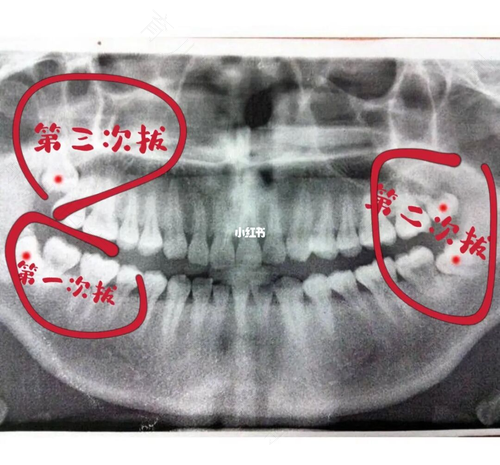

牙齿疼痛,这些小毛病基本上每个人都经历过.现在人们经常会因为智齿的原因去医院拔牙,拔完智齿以后可能会疼痛一段时间,今天我们就来了解一下智齿拔掉后疼多久能好?

拔智齿的时候可能会用到麻醉药,所以拔智齿的过程中不怎么痛,但是等麻醉药的药效过了以后,可能会出现疼痛的症状。一般疼痛的周期会维持在一两天左右,当然不同的个体也要区分这来看。有些朋友对痛感比较敏感,拔牙以后可能会延续比较疼的时间。正常的情况,两到三天疼痛就会消失。

如果拔完牙两到三天以后疼痛还非常剧烈,那么就有可能是干槽症。其主要表现是拔牙后三到五天出现剧烈疼痛,疼痛还有向耳部放射,普通的止痛药根本达不到什么效果,而且口腔里还会出现异味,检查的时候发现拔牙窝空虚,没有血凝块。如果出现了其中的几种情况,那么就需要到医院复诊。

如果有智齿需要拔除的年轻人,建议最好早点进行。因为青少年骨质相对酥松和柔润,牙根比较小,特别好脱位。同时还会伴随着每年牙骨质沉积的情况,拔牙操作也会增加很多难度。